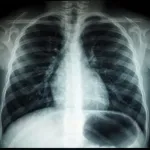

Z outsourcingiem różnego rodzaju usług można spotkać się w dzisiejszych czasach także jeśli chodzi o branżę medyczną. Przykładem takiej usługi jest chociażby teleradiologia, która pozwala, na zlecenie konkretnej jednostki medycznej, zdalnie ocenić i opisać badania obrazowe. Na czym jednak konkretnie polega taka usługa i jakie są korzyści z jej zastosowania?

Zasadniczo rzecz biorąc, teleradiologia nie różni się wiele od innych usług outsourcingowych. Szpital, czy inna jednostka medyczna, nawiązuje współpracę z usługodawcą, takim jak na przykład https://telediag.pl/, któremu zlecane będzie wykonywanie opisów przeprowadzonych w tejże jednostce badań. Za pomocą specjalnego systemu szpitale i przychodnie lekarskie przesyłają wykonane przez siebie obrazy diagnostyczne, zlecają ich opisy, ustalają priorytet i nie tylko. Całość jest bardzo prosta i intuicyjna. Oczywiście opis każdego badania znajdującego się w systemie, szpitale mogą też wykonać samodzielnie.

Opisy takich badań wykonywane są przez doświadczonych radiologów, w trybie, jaki zaleciła dana jednostka medyczna. Tego typu outsourcing usług pozwala przygotować specjalistyczny opis obrazów diagnostycznych w szybki sposób, w praktyce z dowolnego miejsca w Polsce. Teleradiologia pozwala znacząco zoptymalizować czas niezbędny do uzyskania profesjonalnego opisu, a jednocześnie znacząco odciążyć radiologów pracujących w danej jednostce medycznej.